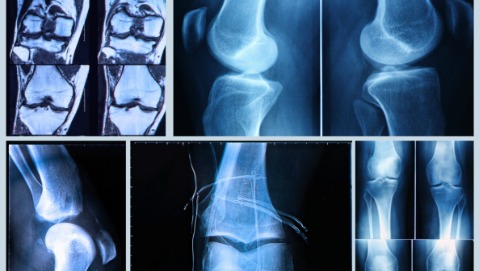

LEGAMENTO CROCIATO - Sottoposti a molteplici sollecitazioni, i legamenti crociati anteriore e posteriore rappresentano il punto debole non soltanto di calciatori e cestisti, ma anche di semplici casalinghe. Oggi tutti gli interventi di ricostruzione - si stima che quelli al legamento crociato anteriore in Italia riguardino quindicimila persone ogni anno - avvengono in artroscopia. Tra le varie tecniche disponibili si sceglie dopo aver valutato le esigenze del paziente, le sue aspettative e il tipo di infortunio subìto. «Ma la tendenza è quella di preferire trapianti con legamenti di tipo biologico, prelevati dal tendine rotuleo o dai flessori della coscia, della stessa persona o no - è quanto emerso dal congresso della Società Italiana di Artroscopia, appena svoltosi a Pesaro -. I tempi di recupero dopo l’intervento variano tra una persona e l’altra, ma l’indicazione per tutti, sportivi e non, è quella di attendere almeno cinque-sei mesi prima di forzare per permettere un corretto recupero biologico».

FOCUS CAVIGLIA - Se per l’artroscopia del ginocchio esiste una consolidata evidenza scientifica, la caviglia è un campo che, nei prossimi anni, riserverà grandi sorprese. «Soltanto nel 2003 è stata confermata la possibilità di operare la caviglia per via artroscopica dalla parte posteriore - dichiara Francesco Lijoi, direttore dell’unità operativa di ortopedia e traumatologia dell’ospedale “Morgagni-Pierantoni” di Forlì -. Quella svolta oggi ci permette di intervenire con efficacia anche sull’articolazione sotto-astragalica, che comanda i movimenti laterali della caviglia. Gli infortuni che interessano questa funzione sono molto frequenti, per cui l’artroscopia rappresenta una soluzione per tutti coloro che sono soggetti a ripetute distorsioni». Per le donne un consiglio pratico: attenzione ai tacchi alti. Usarli tutti i giorni, per molte ore, può dare seri problemi ai tendini della caviglia e al tendine d’Achille, in particolare. I danni per le signore, oltre che da usura, possono essere anche acuti: è il caso delle distorsioni alla caviglia. Nei casi lievi (lesione di primo grado) può bastare l’applicazione di una cavigliera elastica rimanendo a riposo per almeno dieci giorni. Nei casi più gravi invece, si rischia di ricorrere all’intervento, seppur in artroscopia.